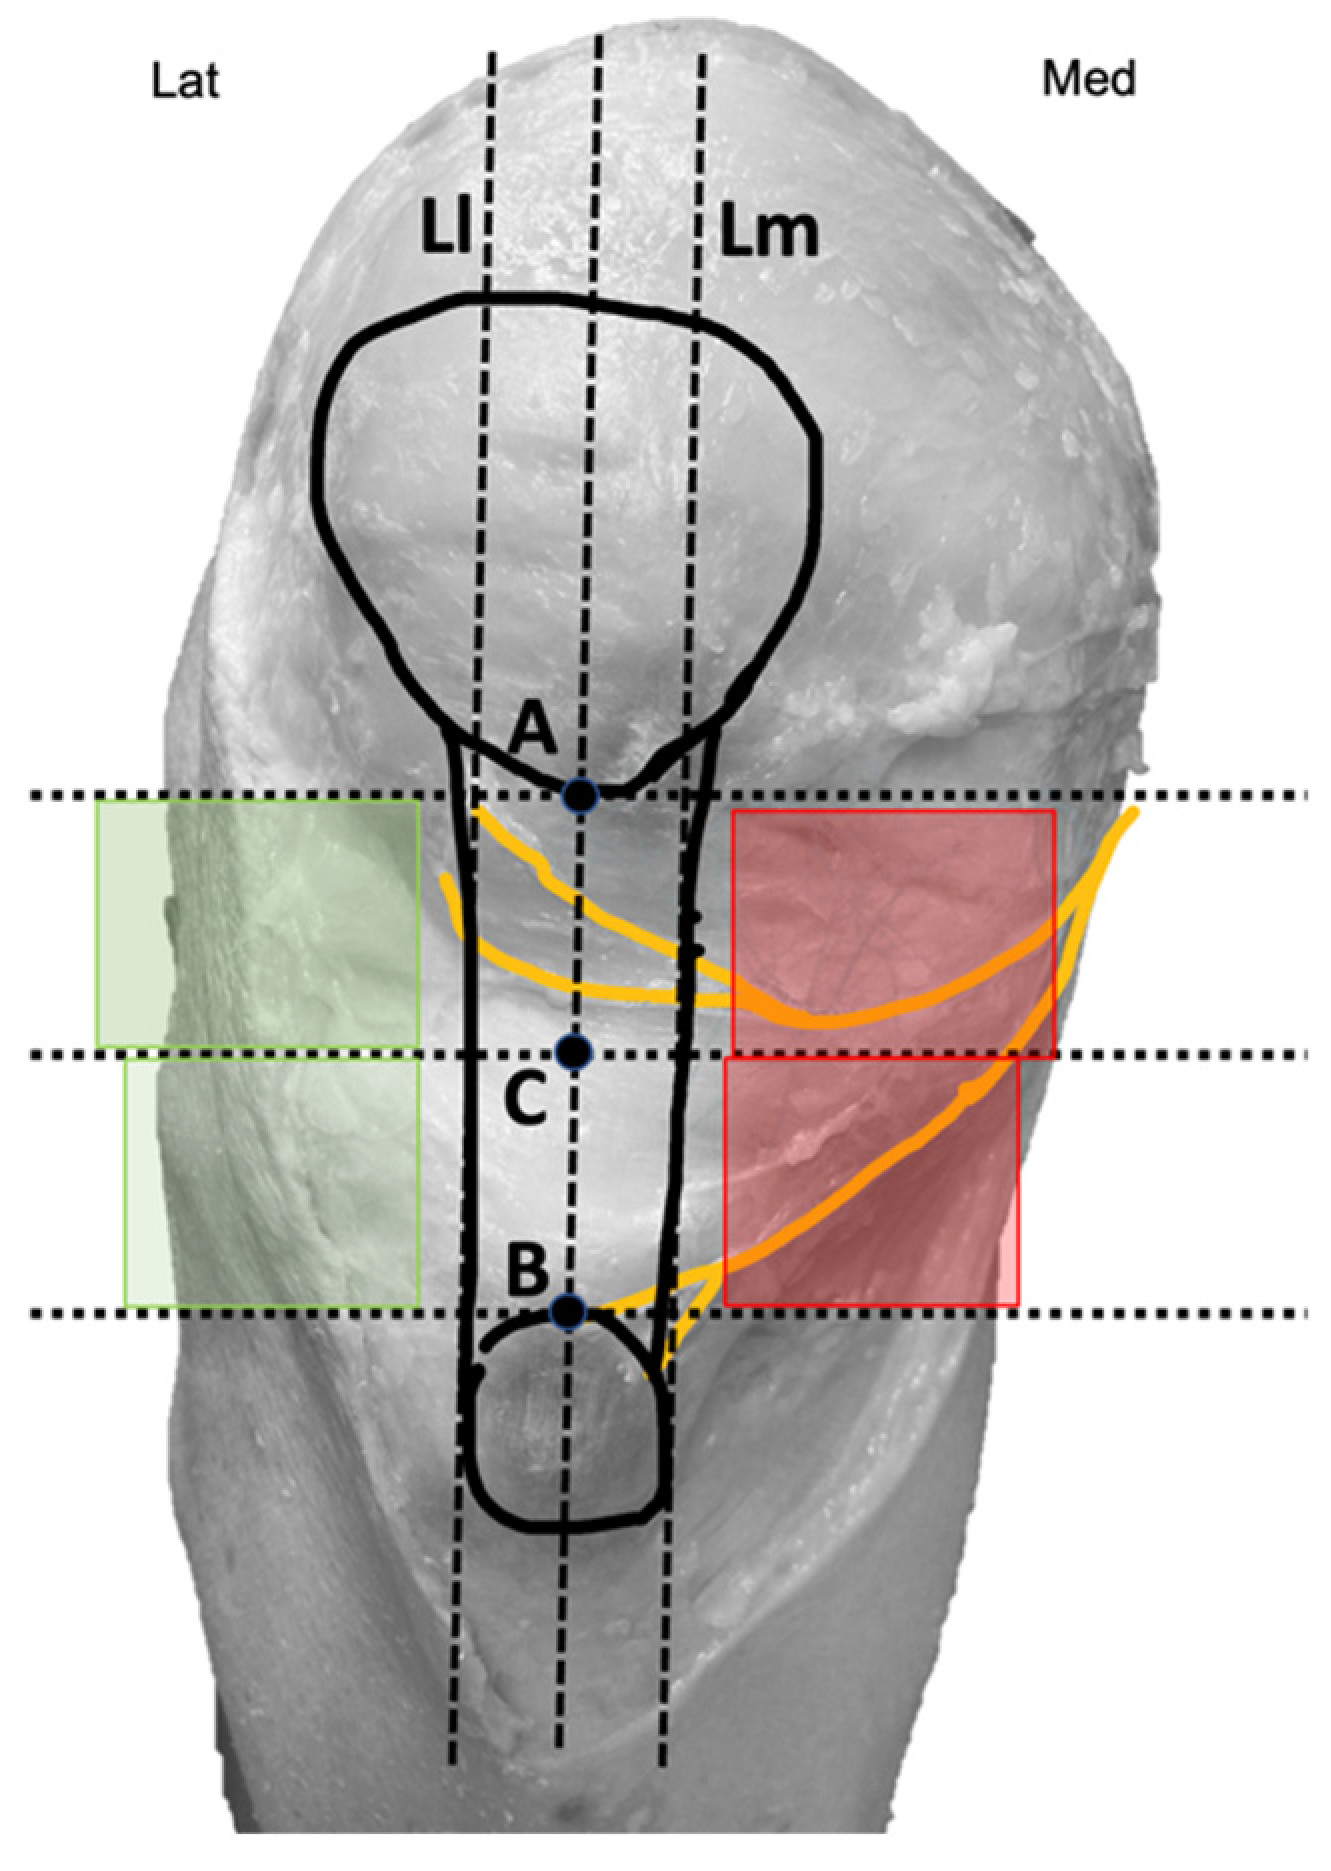

2.3. The Anatomical Procedure on Fresh Cadavers

2.4. The Needling Approach on the Fresh Cadaver

2.5. The Percutaneous Electrolysis Procedure

4.1. The Anatomy of Infrapatellar Nerve Branches

4.2. Ultrasound-Guided Visualization for Needling Approaches